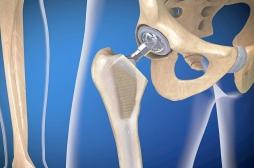

hanche